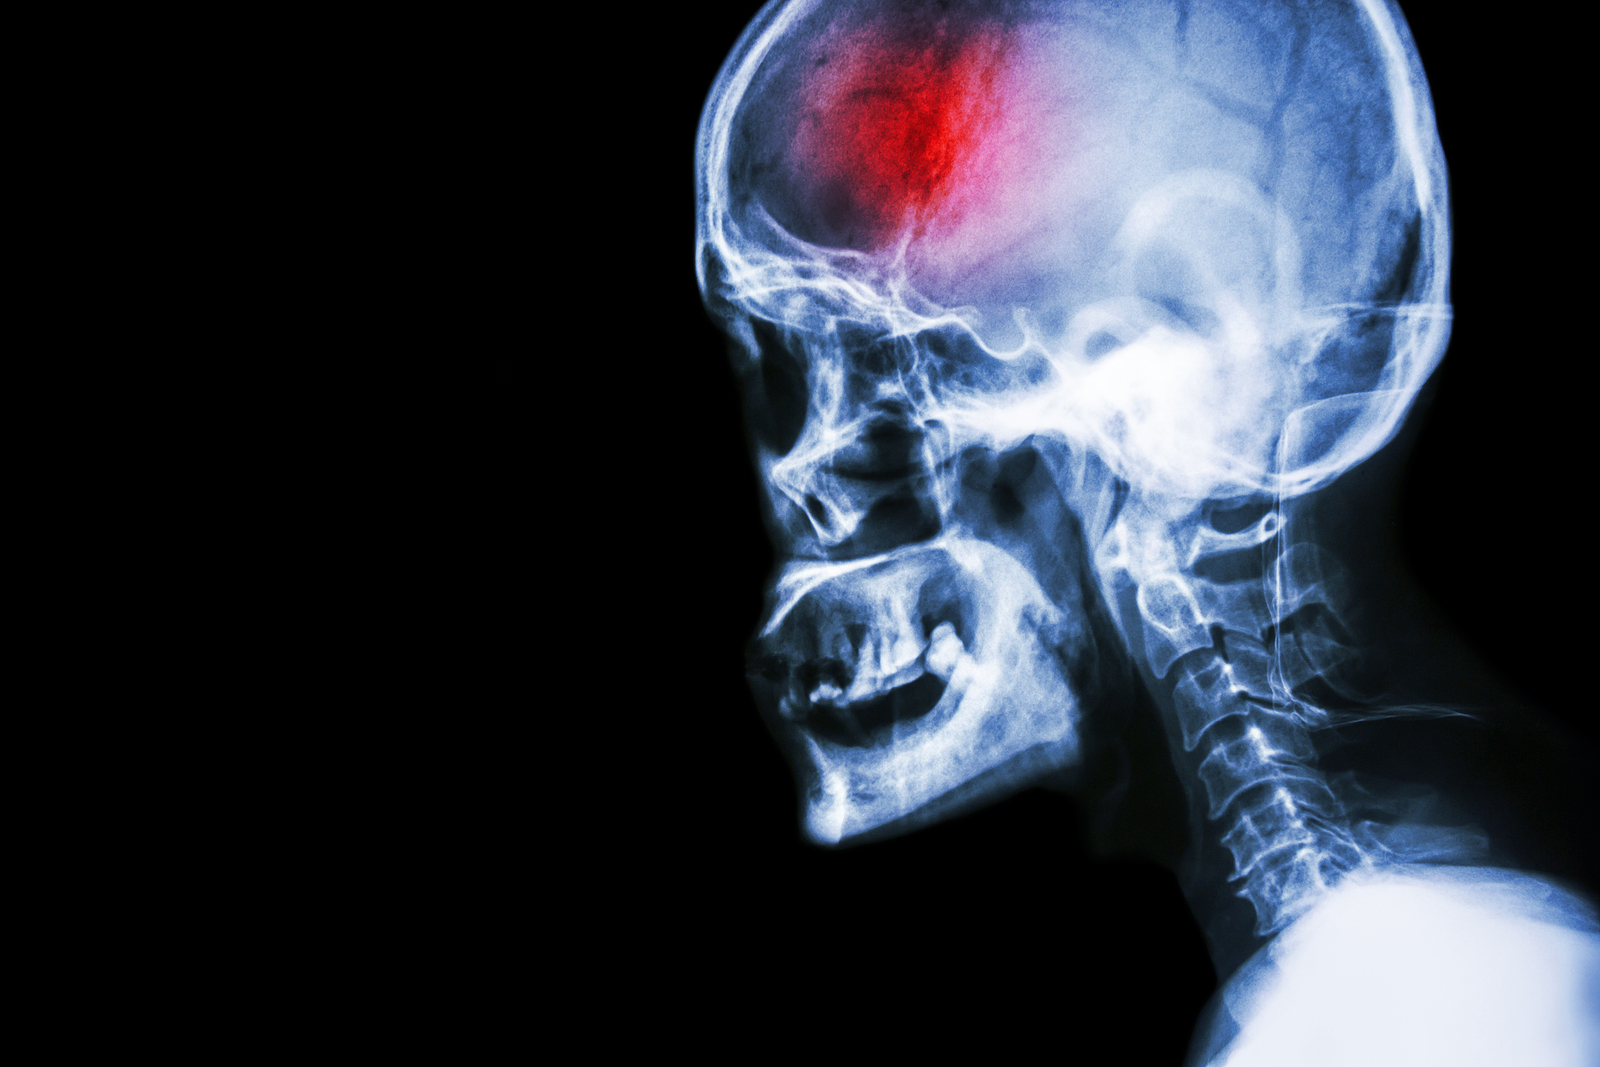

A stroke (previously known as a cerebrovascular accident) when there is a decreased flow of blood to the brain from either a blockage in the blood vessels that supply the brain (ischemic stroke), or a bleed from the blood vessels that supply the brain (hemorrhagic stroke). When the blood flow to the brain is blocked it prevents the brain from getting the needed oxygen and nutrients to function. Without oxygen the brain cells can be permanently damaged or die and the physical and mental functions related to that area of the brain will be affected. A stroke is a medical emergency and rapid treatment is crucial to decreasing the damage caused by a stroke.

• Ischemic stroke: a stroke that is caused by a blockage (clot) that disturbs the blood flow to the brain.

• Hemorrhagic stroke: a stroke that is caused by a bleed that disturbs the blood flow to the brain and puts pressure on the surrounding tissue.

• Transient ischemic attack: often referred to as a “mini-stroke” or TIA, where the blood flow to the brain is temporarily disturbed and as a result causes temporary signs and symptoms of a stroke that resolve quickly .

A bleed in the brain can occur due to several reasons. Aneurysms are balloon-like bulges in the brain that can burst causing a bleed. Aneurysms can be a malformation you are born with or can occur due to atherosclerosis.

Arteriovenous malformations (AVMs) are malformations that someone is born with which cause poorly formed arteries and veins within the brain. Having an AVM increases the chances of these vessels breaking open and causing a stroke. Bleeding in the brain disrupts the blood supply to the brain tissue along its path as well as causes pressure from the escaped blood to any surrounding tissue.